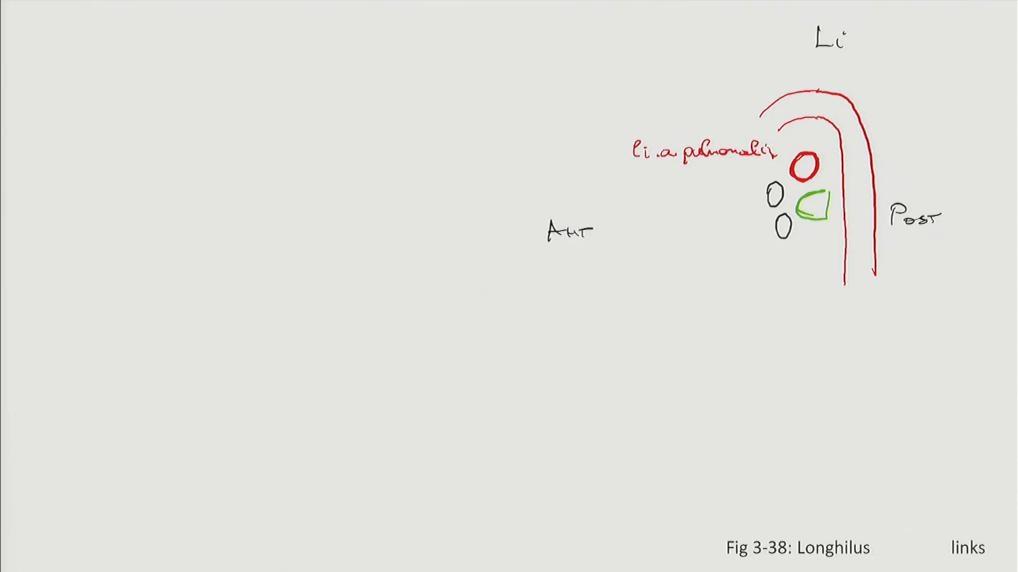

Fig 3.38b: Longhilus links

aorta a. pulmonalis sinistra vv. pulmonales (zwart) bronchus

Grays: Fig 3.46